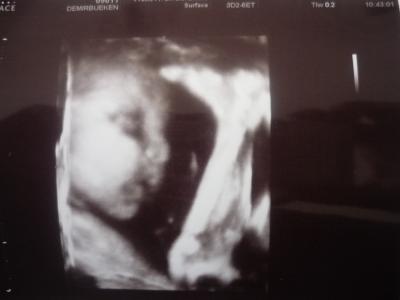

http://www.rund-ums-baby.de/include/images/emoticons.gif war echt lustig, die kleine wollte sich erstmal mit dem CTG-Gerät nicht anfreunden anschließend wurde ein US gemacht und die FÄ fing an zu lachen.... die kleine liegt zwar schon mit dem Kopf richtig, also unten, aber hat sich ziemlich verenkt. Sie hat nämlich Ihre Füße mitgenommen..... Ich muß mir aber keine Sorgen machen, kann sich alles noch ändern !!!!!! Größe weiss ich leider nicht aber sie wiegt ca. 1250 gramm in der 28+0 SSW

Bild zu FA-Besuch - Forum für Mai - Mamis